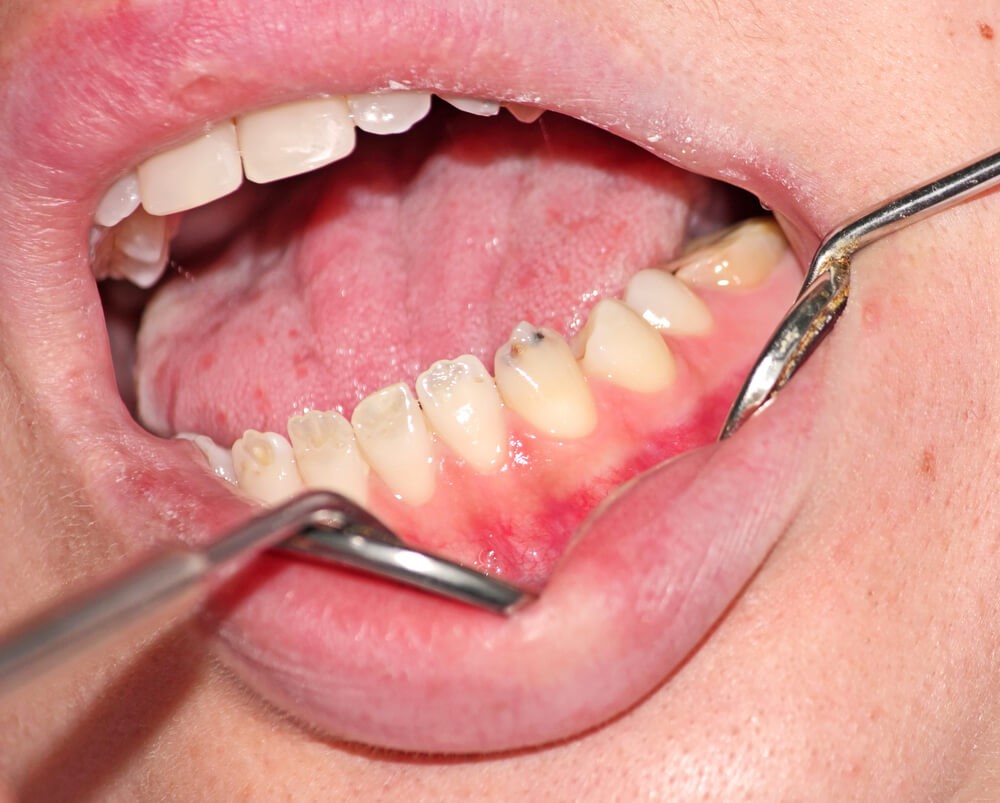

همانطور که گفته شد، برخی از علائم قابل مشاهده هستند، اما تشخیص برخی دیگر دشوارترند و تا زمانیکه باعث مشکلات عمده دندانپزشکی نشوند، مورد توجه قرار نمیگیرند. داشتن مینای دندان نازک میتواند منجر به موارد زیر شود:

- حساسیت به گرما و سرما

- حساسیت به اسیدهای موجود در غذا و نوشیدنی

- حفظ باکتریهای مضر

- افزایش آسیبپذیری در برابر پوسیدگی دندان و حفرهها